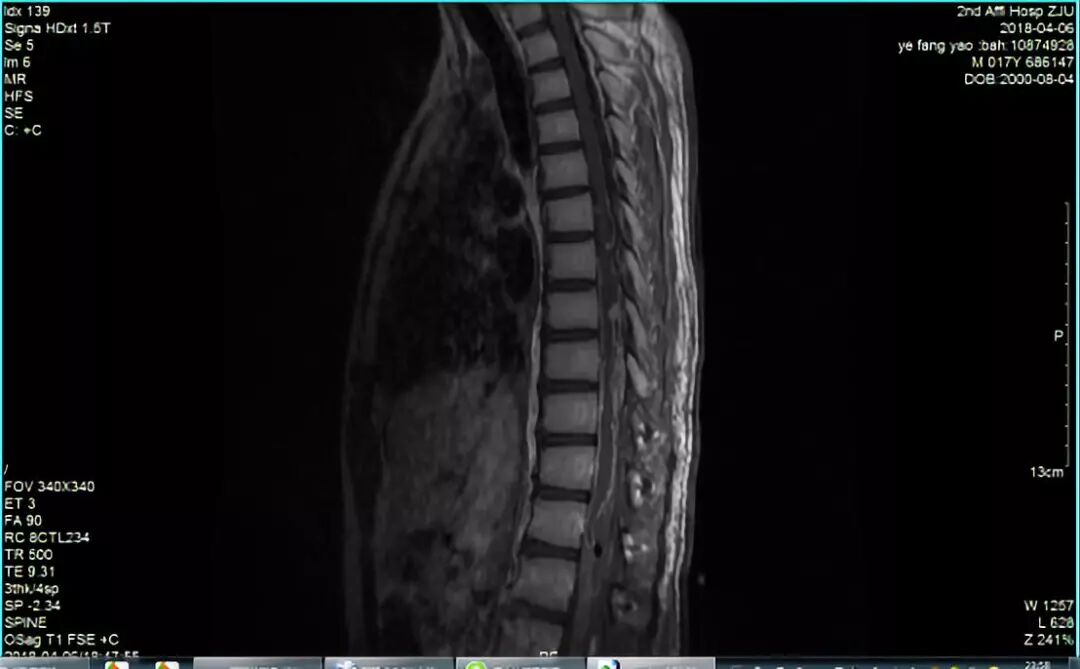

入院后查腰椎增强MRI(2018-04-02)提示:胸10-腰1椎体水平椎管内肿瘤,首先考虑室管膜瘤,椎管内多发播散转移。加行全脊柱及头颅增强MRI提示:小脑、第四脑室、颈、胸、腰段椎管内广泛播散转移灶。2018-04-04行[胸10-腰1]椎管内病损切除术,术中采用铣刀胸10-腰1全椎板成形打开椎管后,见脊膜膨隆,张力较高。显微镜下切开硬脊膜及蛛网膜,见脊髓表面覆盖红色肿瘤样组织,部分沿软膜播散,与脊髓边界欠清, 肿瘤色灰红,质软,部分呈粘稠液状,血供一般,整体约10cm*2cm*2cm大小,分块切除大部肿瘤后,发现肿瘤与终丝关系密切,离断终丝,逐步清除散在的粘连于蛛网膜及神经根的肿瘤。缝合硬脊膜,以二孔钛片回纳椎板重建椎管后结束手术,标本送常规病理检查。术后查体:双下肢肌力基本同术前,肌张力正常,双下肢浅感觉减退,深感觉正常,病理征阴性。

图1. 入院MRI检查。A、 B: 胸腰椎增强MRI提示胸10-腰1椎管内占位,考虑室管膜瘤(A: 矢状面,B: 横断面);C: 头颅增强MRI提示颅内转移灶;D颈椎增强MRI提示:颈髓亦有播散转移。